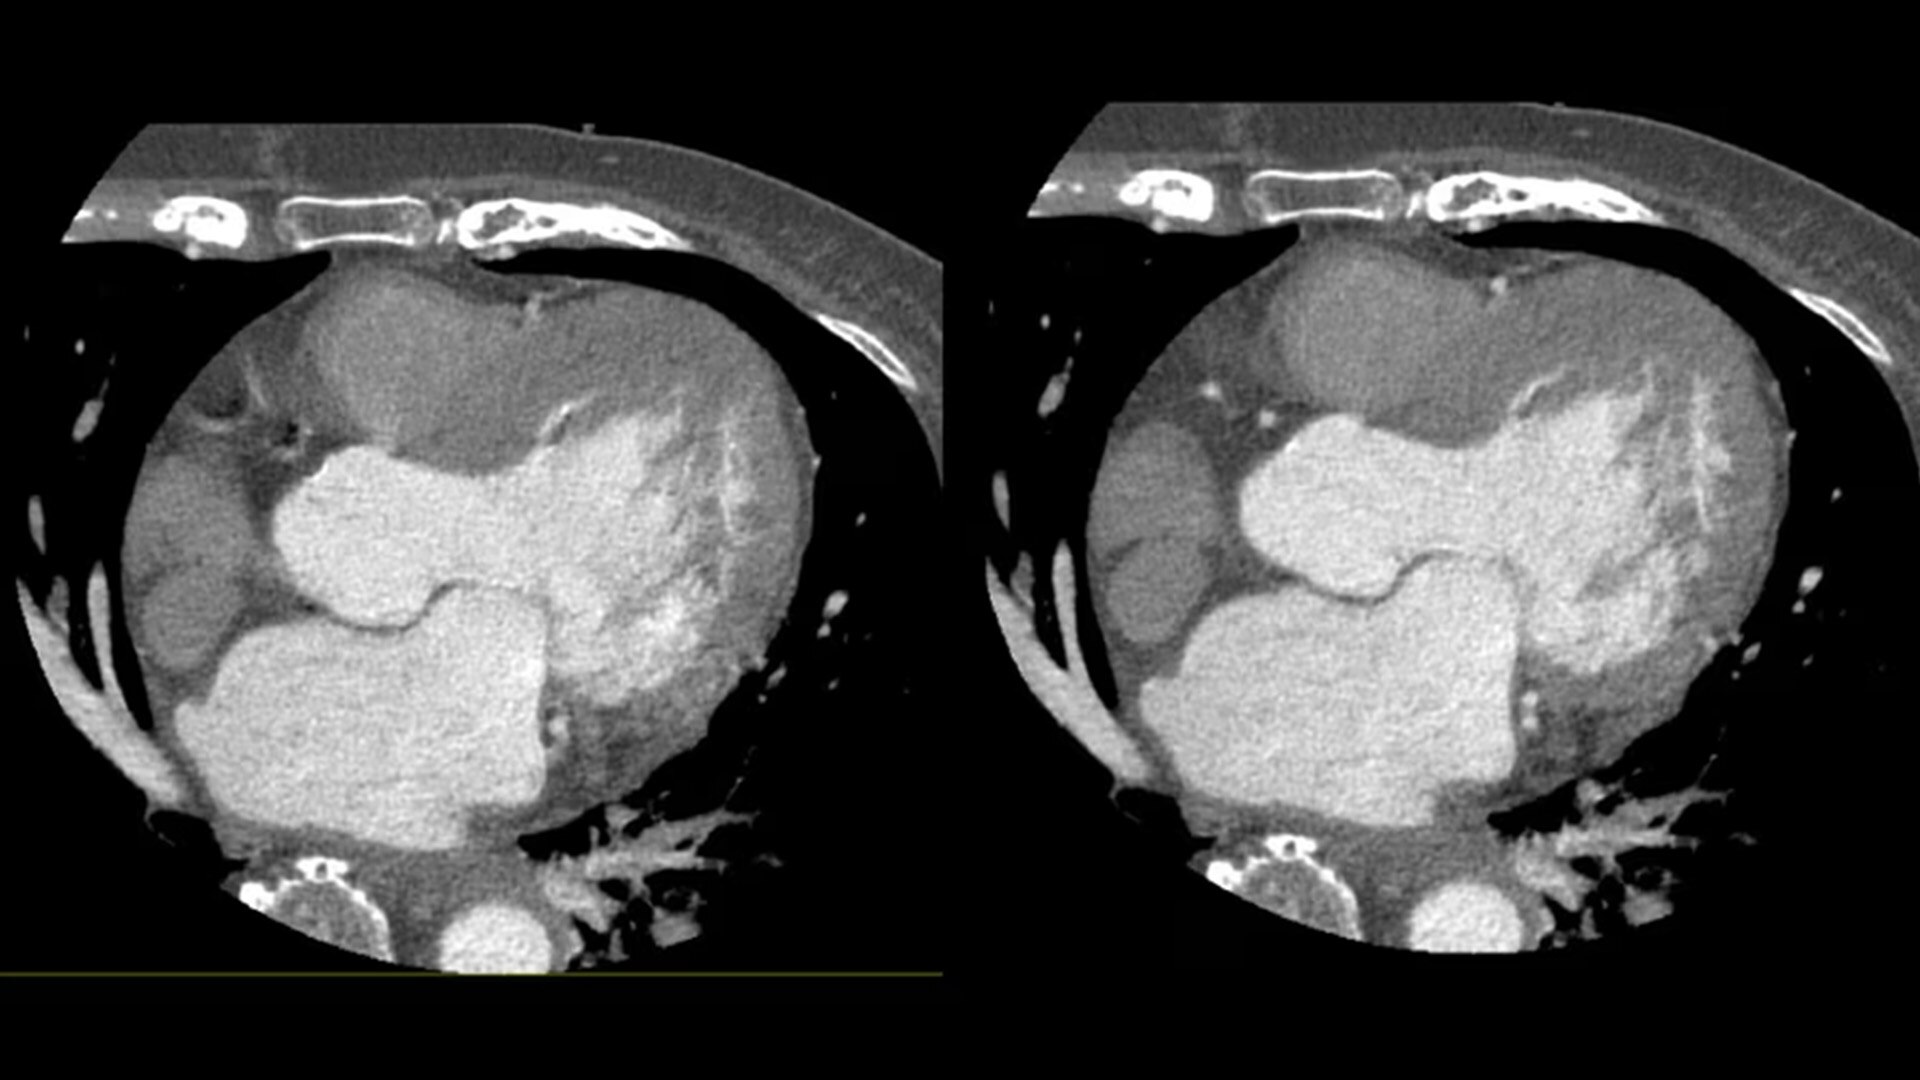

SnapShot Freeze 2

Intelligent and automated whole-heart motion correction for enhanced Cardiac CT imaging.

Motion correction

6x reduction in motion artifacts1

Temporal resolution

19.5 msec effective temporal resolution at 0.23s/rotation gantry speed2